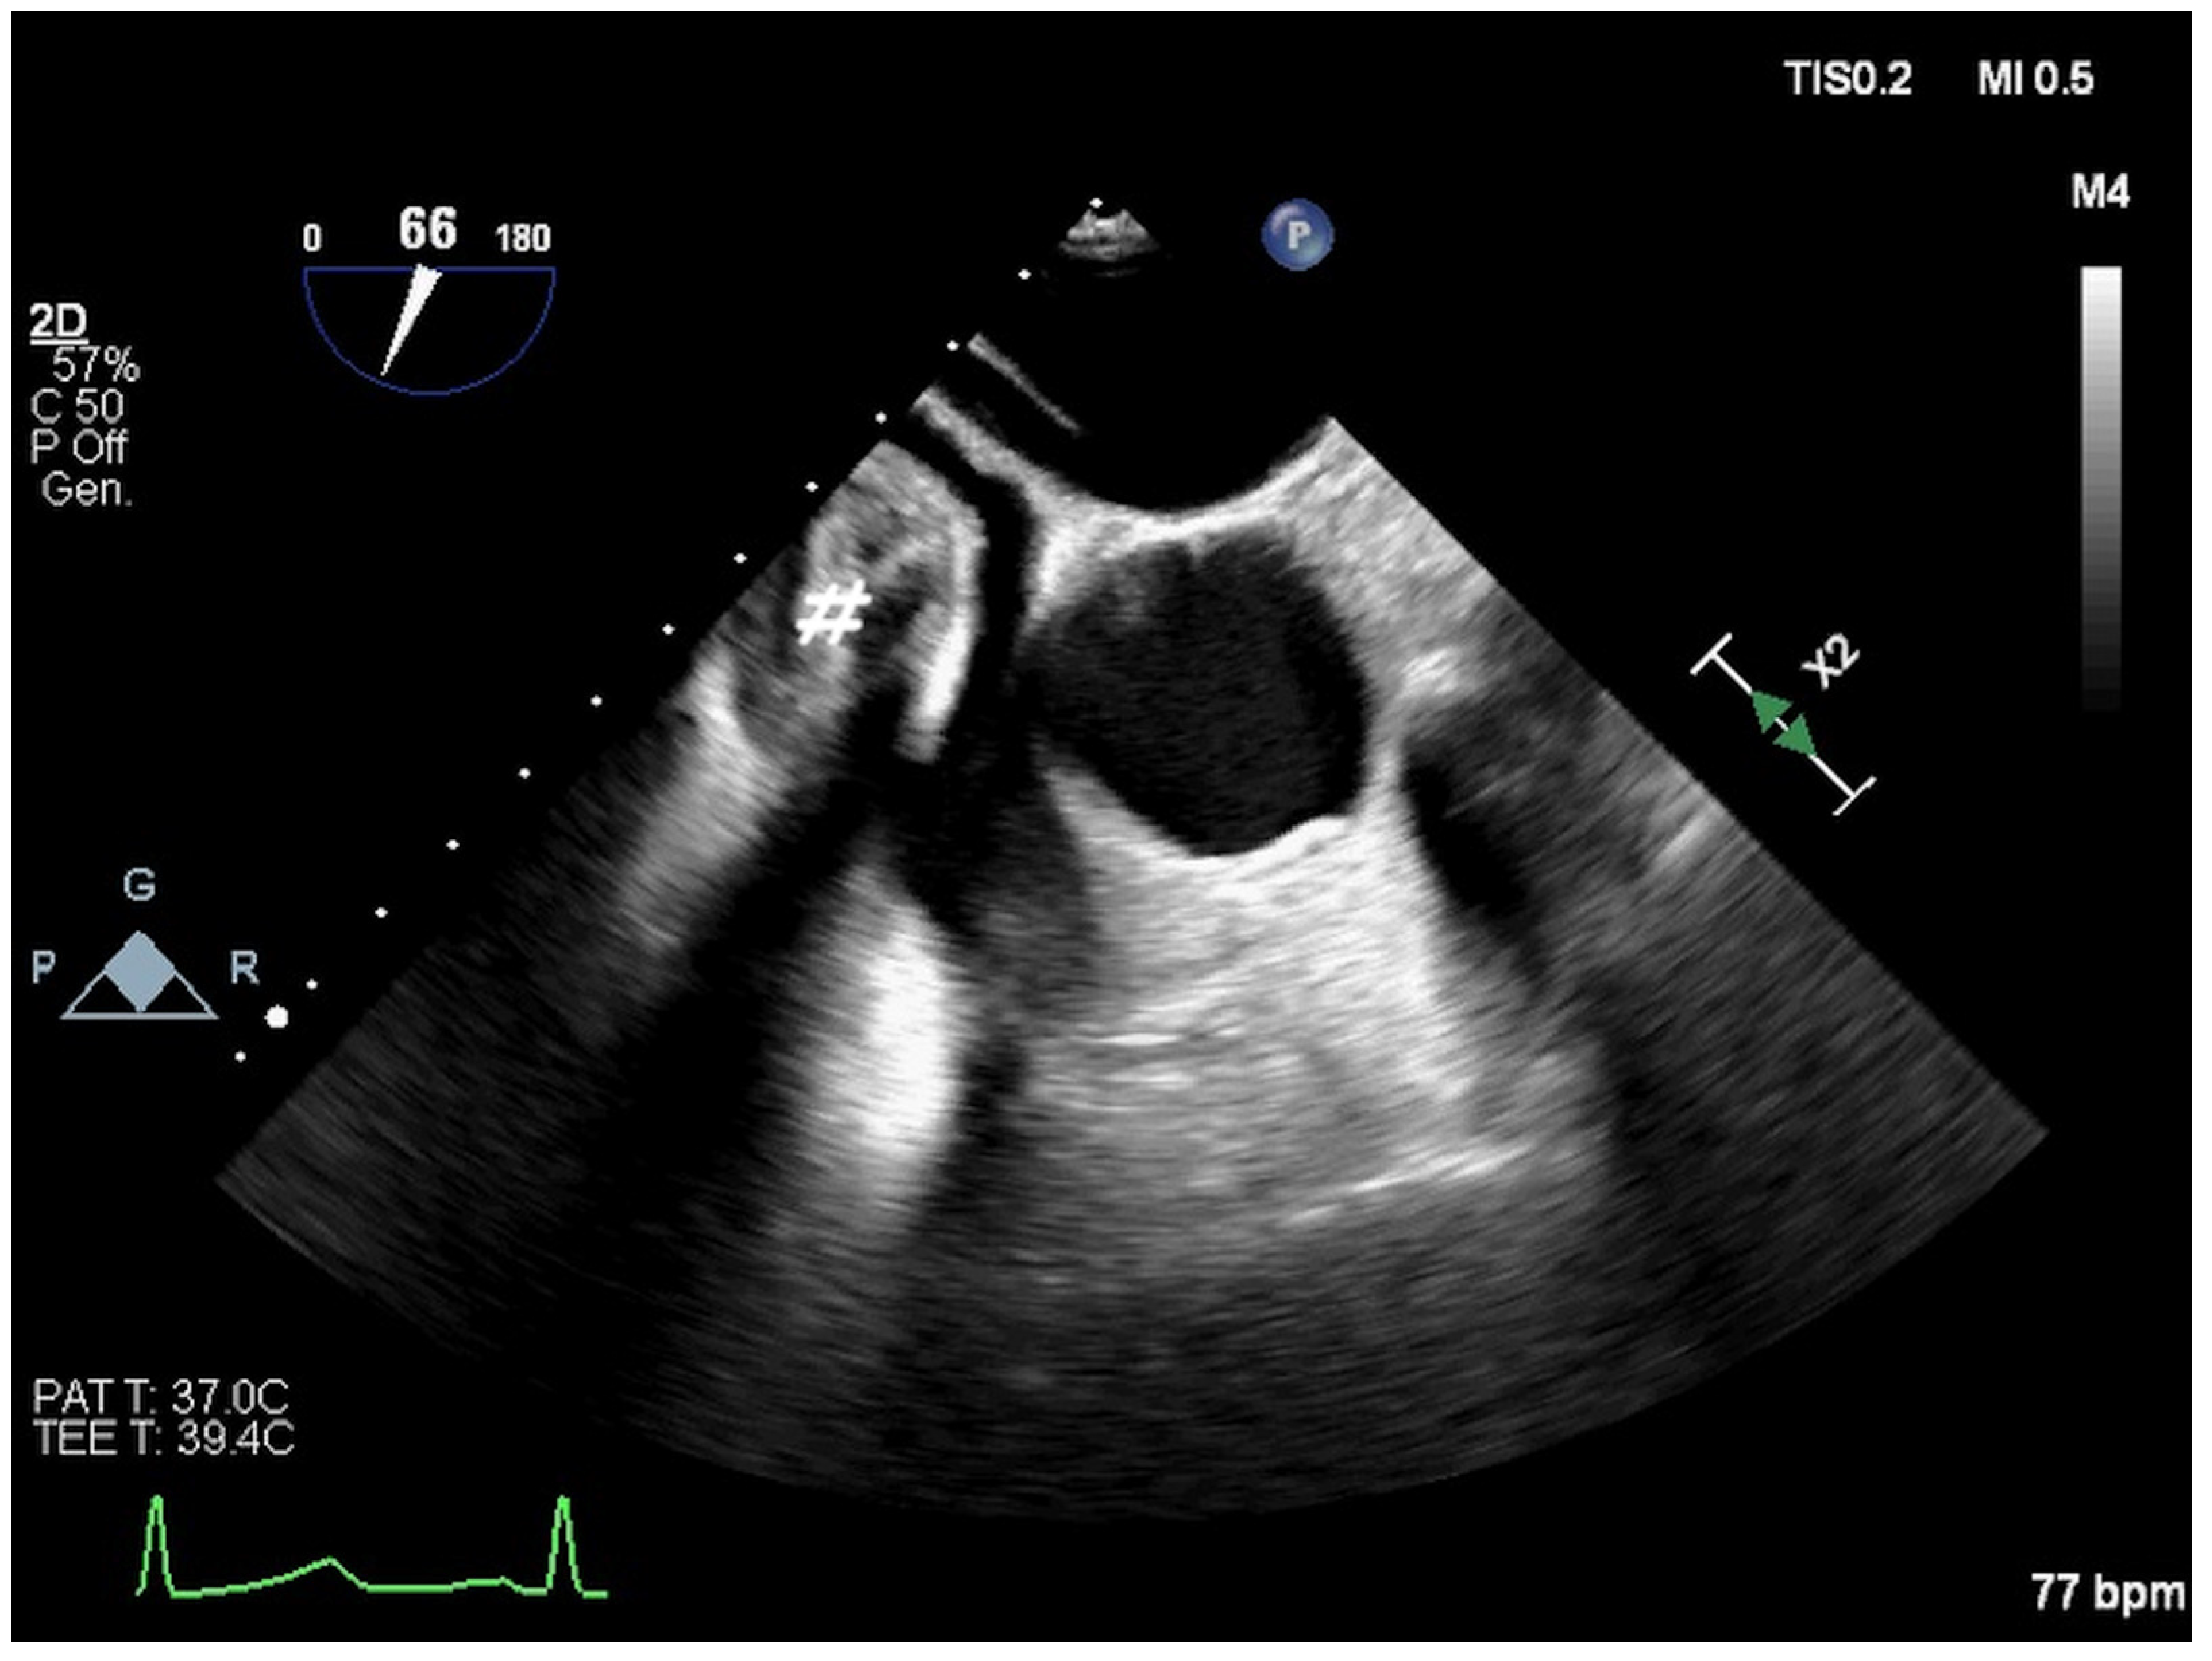

2. Atrial Septal Defect Closure